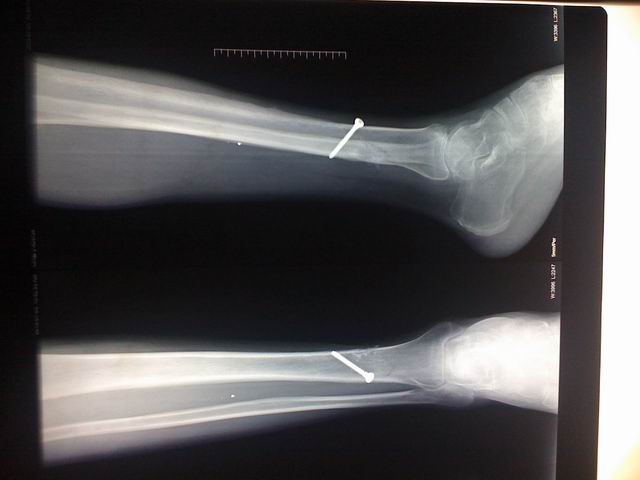

宗亲们好,这是过来拍的片子。

调整大小 IMG_0031.jpg

调整大小 IMG_0032.jpg

调整大小 IMG_0033.jpg